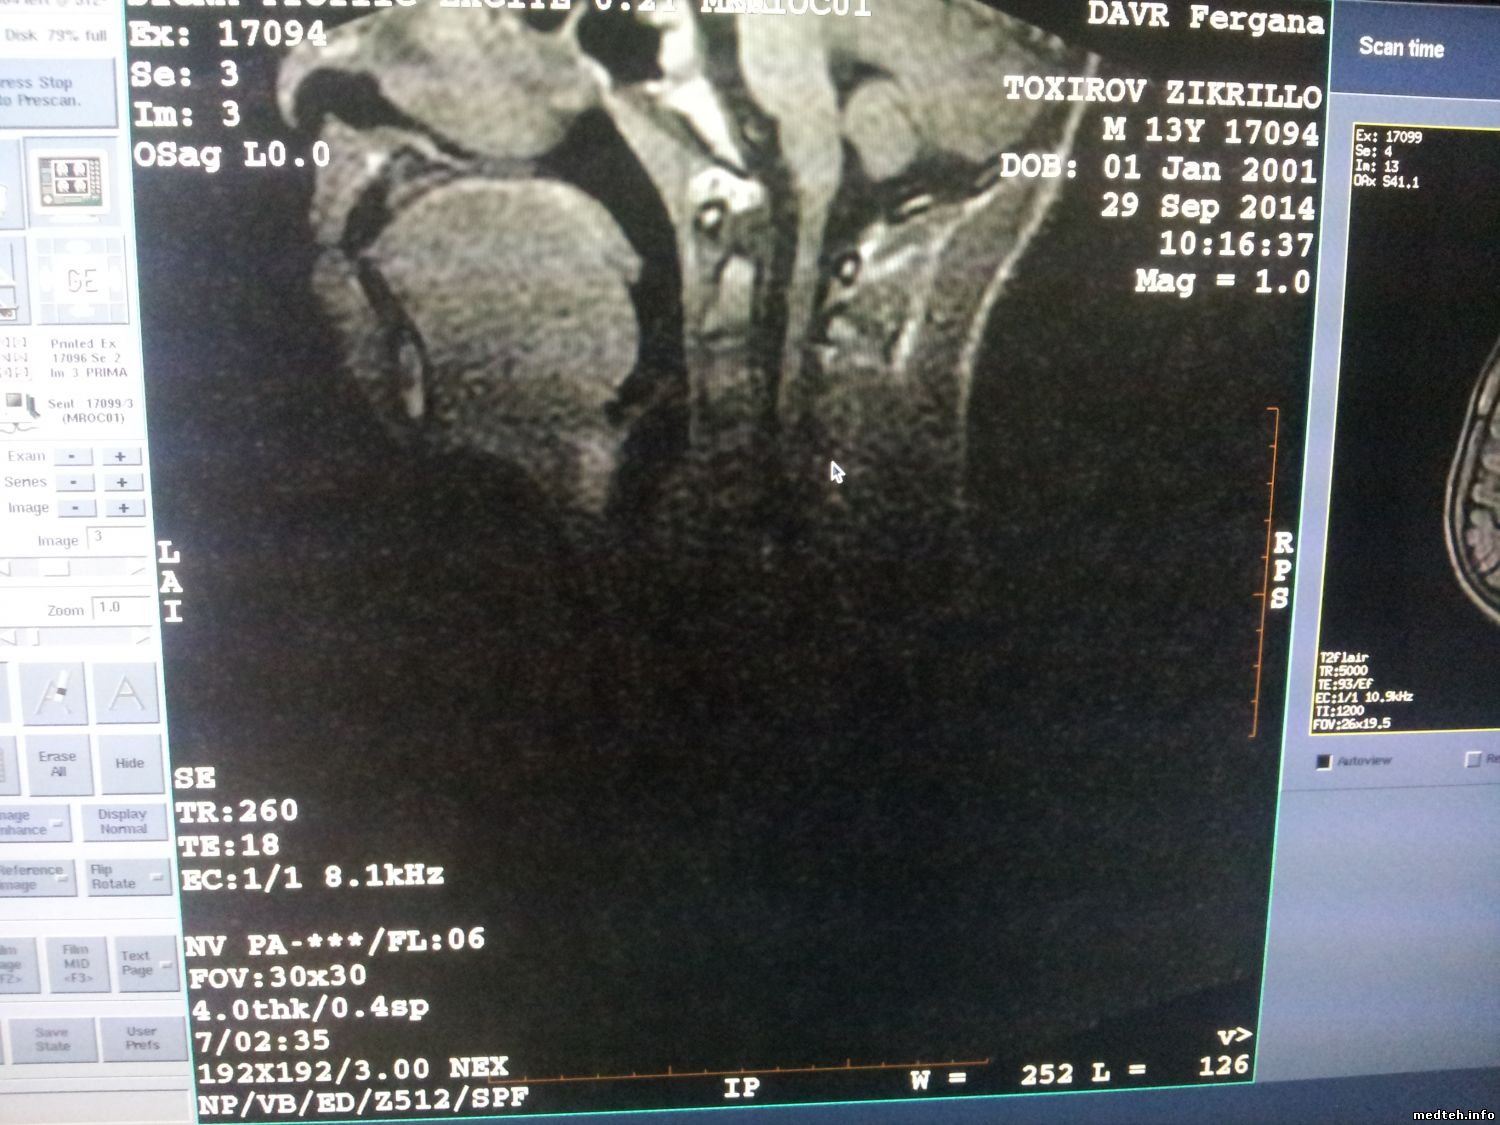

Аппарат фирмы GE Signa Profile при съемки шеи на катушке нижней Neurovascular array дает артефакт (затемнение). На другой катушки CTL coil снимки отличные. посоветуйте что делать.

забыл снимок закрепить.

6070665.jpg (169.9 Kb)

Видно, что нет сигнала от одного (или нескольких) каналов. Точнее не скажу - с GE дло не имел. Но принцип работы одинаковый на всех МРТ.

однозначно нет сигналов каналов смотреть катушку! Разобрав можно прозвонить контуры катушки, прозвонить кабель катушки на разрыв!